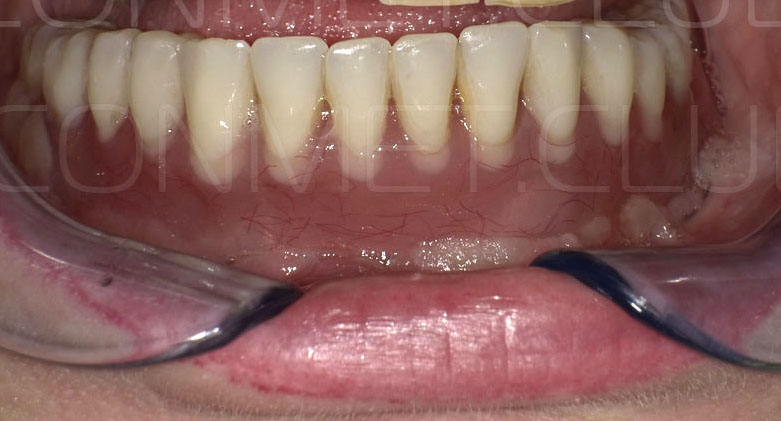

Сама же операция длиться 20-50 минут в зависимости от количества утраченных зубов. В процессе этой операции, после проведенной местной анестезии, делается разрез на слизистой, она приподнимается и субпериостальный имплантат укладывается на кость. После этого рана фиксируется несколькими швами и все! Через 10-14 дней мягкие ткани срастаются и надкостница надежно удерживает имплантат на месте. Нет необходимости ждать несколько месяцев, как это бывает в случае с внутрикостными винтовыми имплантатами.

Новые, искусственные зубы фиксируются к этому имплантату стандартными, трансокклюзионными винтами на 1-14 день (в данном клиническом случае на 5 сутки) и по существу являются несъемными!

И в-четвертых: небольшой фрагмент из операции по восстановлению всех утраченных зубов на верхней челюсти. По сути эта операция полностью повторяет протокол и этапность операции представленной в первой части статьи, за исключением того, что искусственные зубы были зафиксированы сразу после операции. Со слов самой пациентки, процесс жевания был совершенно безболезненным с самого первого дня.

Результаты проведенных в 2017-2018 году операций субпериостальной имплантации показали их высокую эффективность, очень быструю адаптацию пациентов к новым зубам и отсутствие послеоперационного болевого синдрома. Интересной особенностью является труднодиагносцируемая, но точно присутствующая микроподвижность имплантатов спустя 6-12 месяцев. Учитывая данную особенность надо категорически избегать объединения субпериостальных имплантатов с естественными зубами или внутрикостными имплантатами!